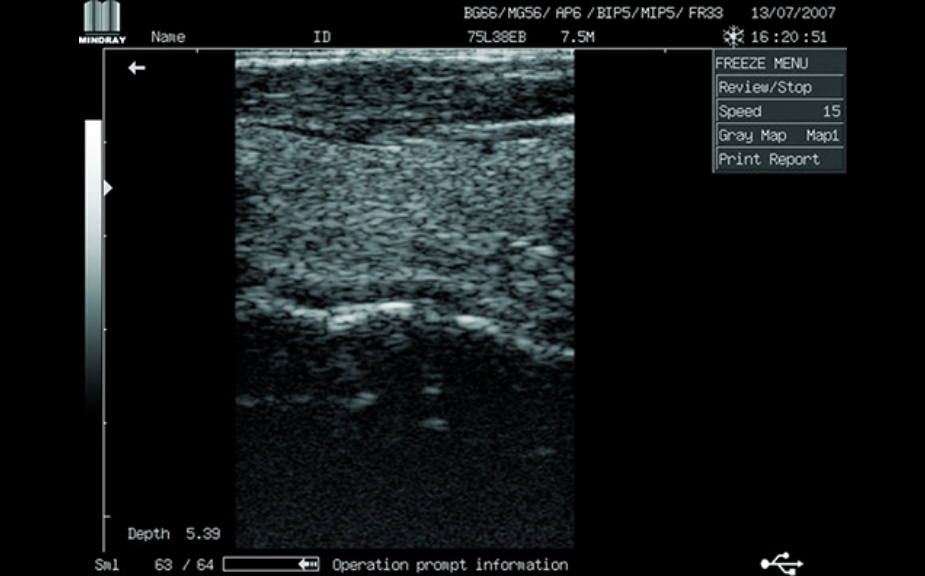

Clinical Images